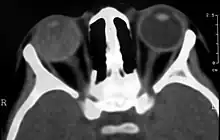

Computed Tomography image of a patient with Coats' disease, showing total exudative retinal detachment in the right eye

On CT, the globe appears hyperdense compared to normal vitreous due to the proteinaceous exudate, which may obliterate the vitreous space in advanced disease. The anterior margin of the subretinal exudate enhances with contrast. Since the retina is fixed posteriorly at the optic disc, this enhancement has a V-shaped configuration.[2]